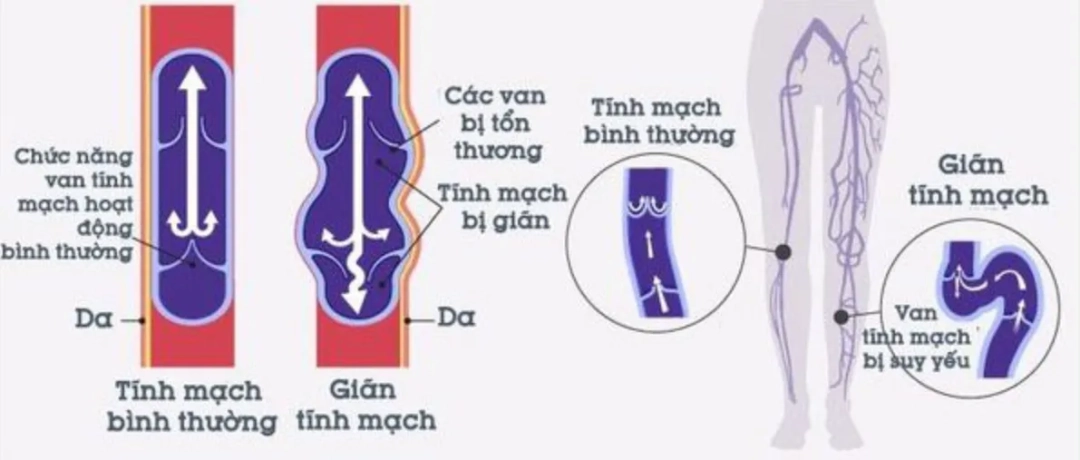

Suy giãn tĩnh mạch chi dưới mãn tính là bệnh lý phổ biến do suy giảm chức năng hệ tĩnh mạch, gây ứ đọng máu ở chân. Bệnh có thể do di truyền, huyết khối, chèn ép hoặc thai kỳ. Chẩn đoán dựa vào...

Suy giãn tĩnh mạch chi dưới mãn tính là bệnh lý phổ biến do suy giảm chức năng hệ tĩnh mạch, gây ứ đọng máu ở chân. Bệnh có thể do di truyền, huyết khối, chèn ép hoặc thai kỳ. Chẩn đoán dựa vào...